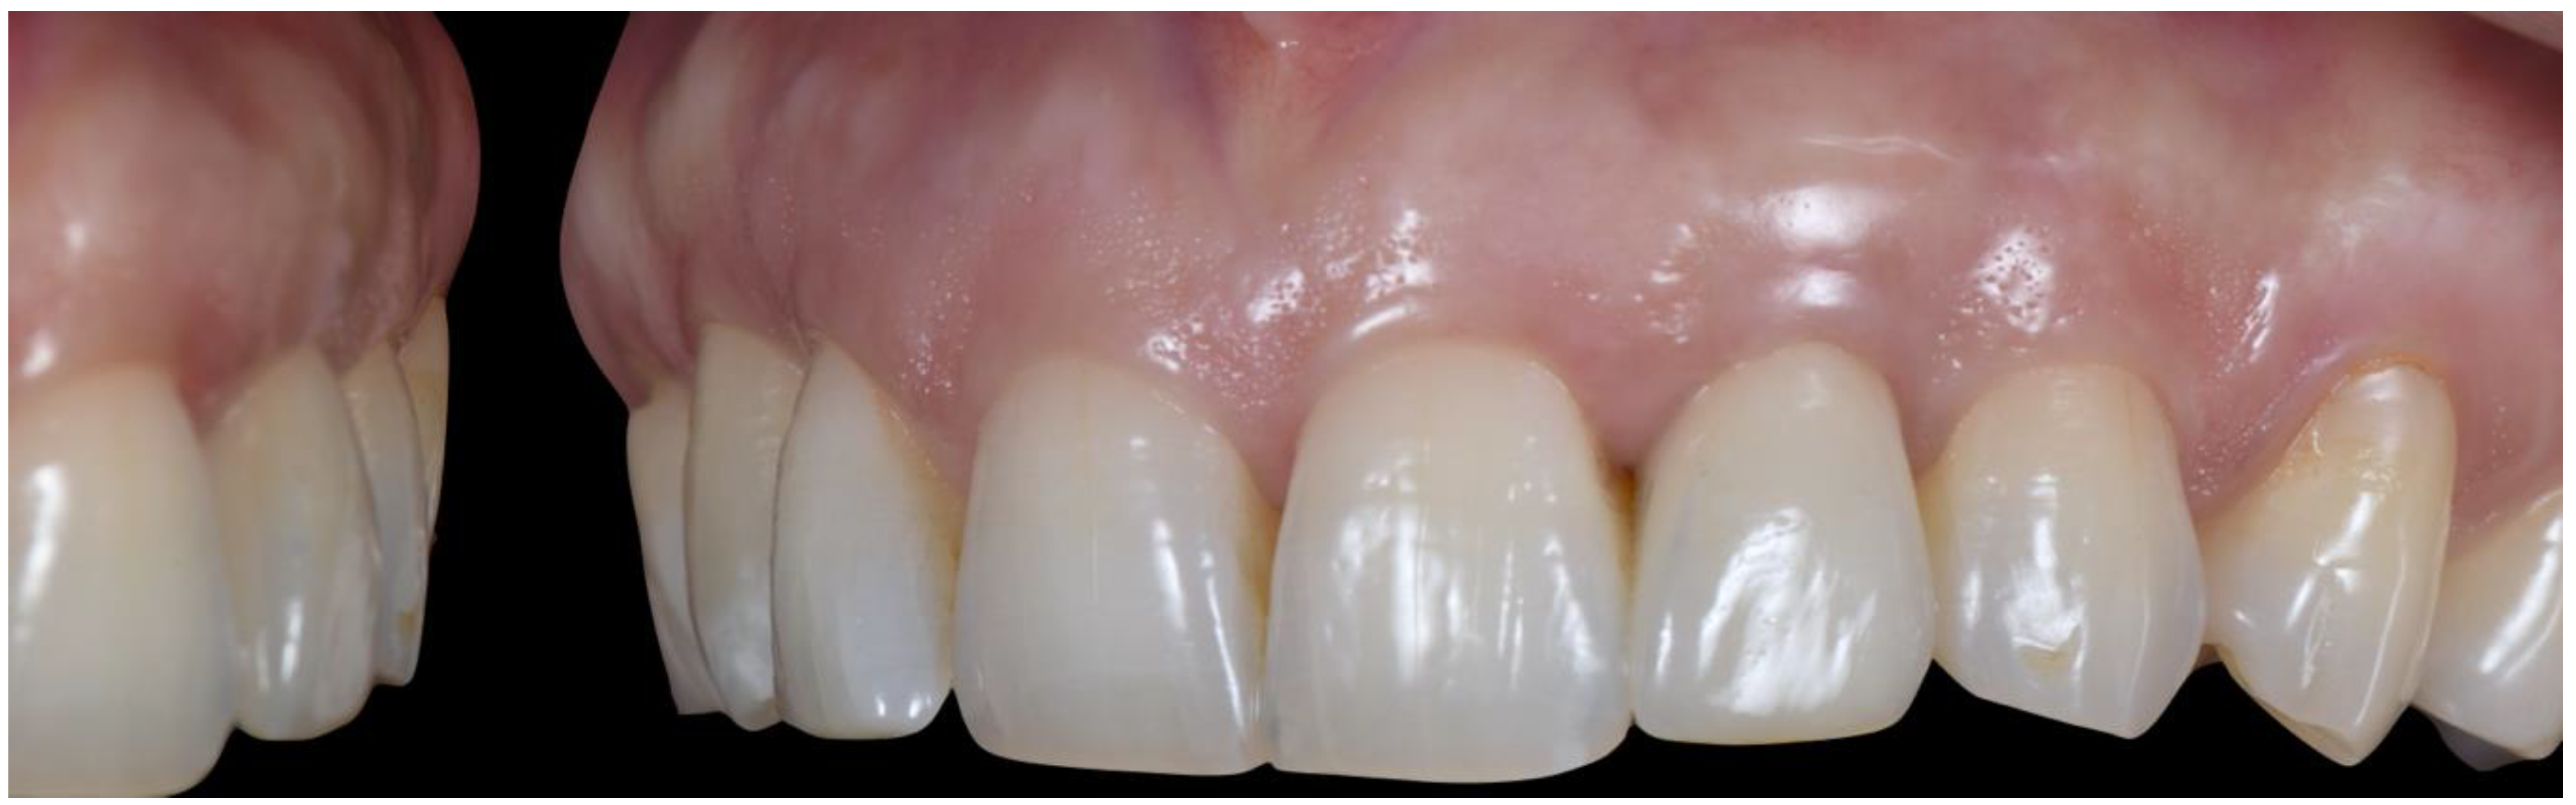

2.4. Transitional Restoration Stage

2.5. Impression Stage

2.6. Lab Stage

2.7. Prosthesis Delivery